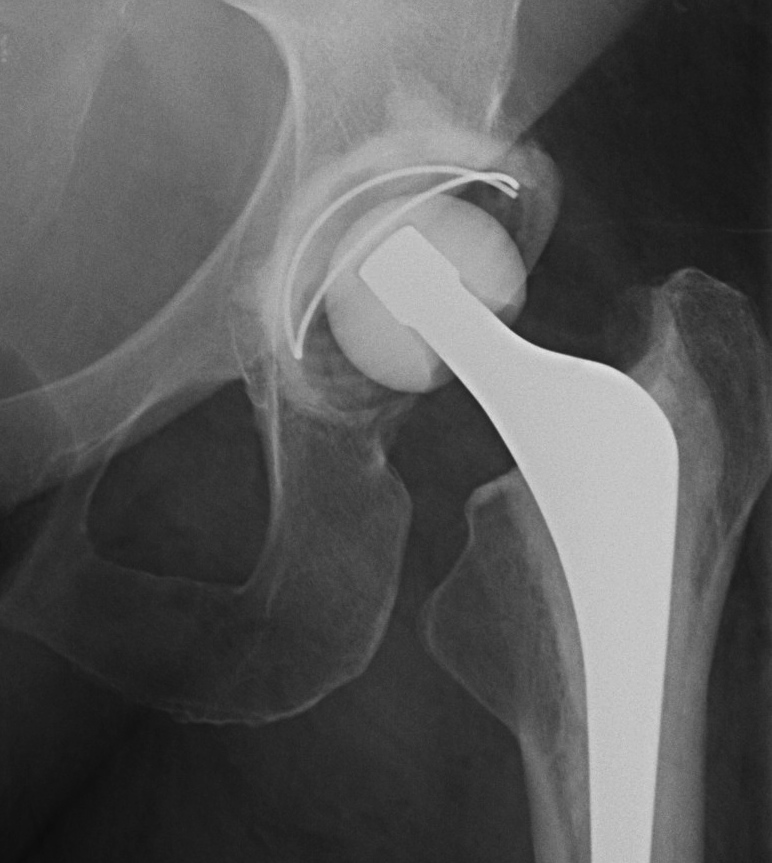

Ceramic on poly THA S&N oxinium on poly S&N ceramic on ceramic